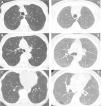

(A–F) Diffuse lung disease at baseline LDCT. Advanced destructive pulmonary emphysema (A–C) in a 65-year-old man from NLST who died of respiratory disease (ICD code J449) 835 days after randomization. Interstitial lung disease (D–F) in a 73-year-old man from NLST who died of respiratory disease (ICD code J849 – interstitial pulmonary disease unspecified) 2462 days after randomization.